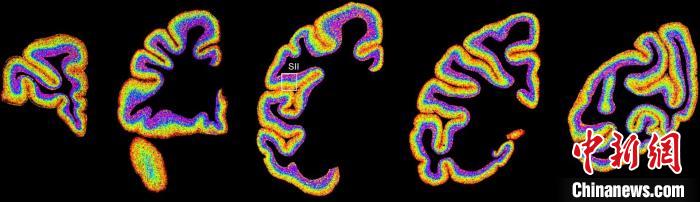

圖為不同類型細(xì)胞在獼猴大腦上的分布切片?!≈袊茖W(xué)院腦科學(xué)與智能技術(shù)卓越創(chuàng)新中心 供圖

李澄宇說,科研人員做的事情好似“查戶口”,也就是搞明白猴腦里有哪些細(xì)胞、這些細(xì)胞在哪些位置。搞明白這些就形成了一個大的數(shù)據(jù)集,科研團(tuán)隊挖掘這個數(shù)據(jù)集,發(fā)現(xiàn)了很多有意思的現(xiàn)象:比如,興奮性神經(jīng)元、抑制性神經(jīng)元以及非神經(jīng)元在大腦皮層中的分布呈現(xiàn)明顯的特異性,也就是不同細(xì)胞“住”哪,有一定規(guī)律。